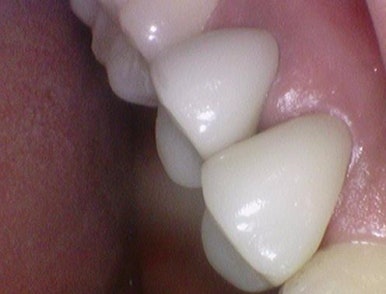

충치가 심한 치아를 크라운(지르코니아 크라운)으로 해서 자연스럽게 만든 모습. 시청역치과